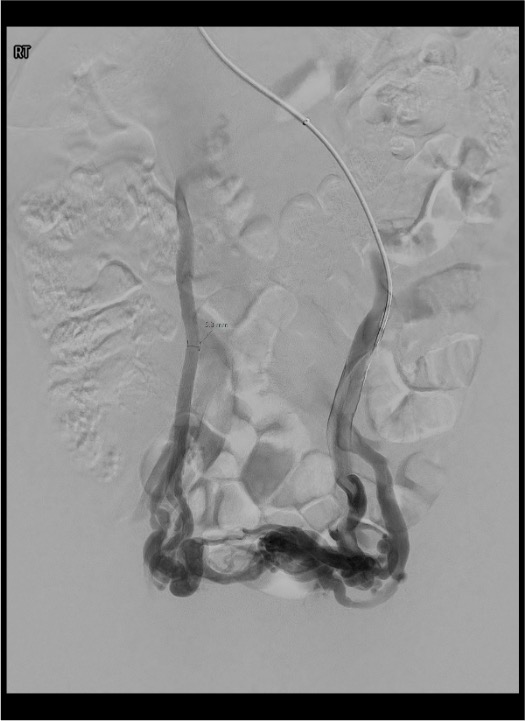

- Venographic diagnosis criteria: tortuous pelvic vein >4 mm diameter, poor flow (<3 cm/s), distended communicating veins, retrograde filling on Valsalva

Left Ovarian Vein

- Takeoff from LRV: gooseneck angulation at the LRV-LOV junction; best approached coaxially from RIJ; catheter should point inferiorly to engage the ostium

- Diameter: 5–8 mm with reflux; normal is <5 mm

- Reflux pattern: contrast flows retrograde into broad ligament and parametrial plexus during Valsalva or spontaneously in severe cases

- Nutcracker sign: spontaneous reflux into left ovarian vein during LRV injection without Valsalva; LRV diameter <6 mm at aorto-mesenteric segment